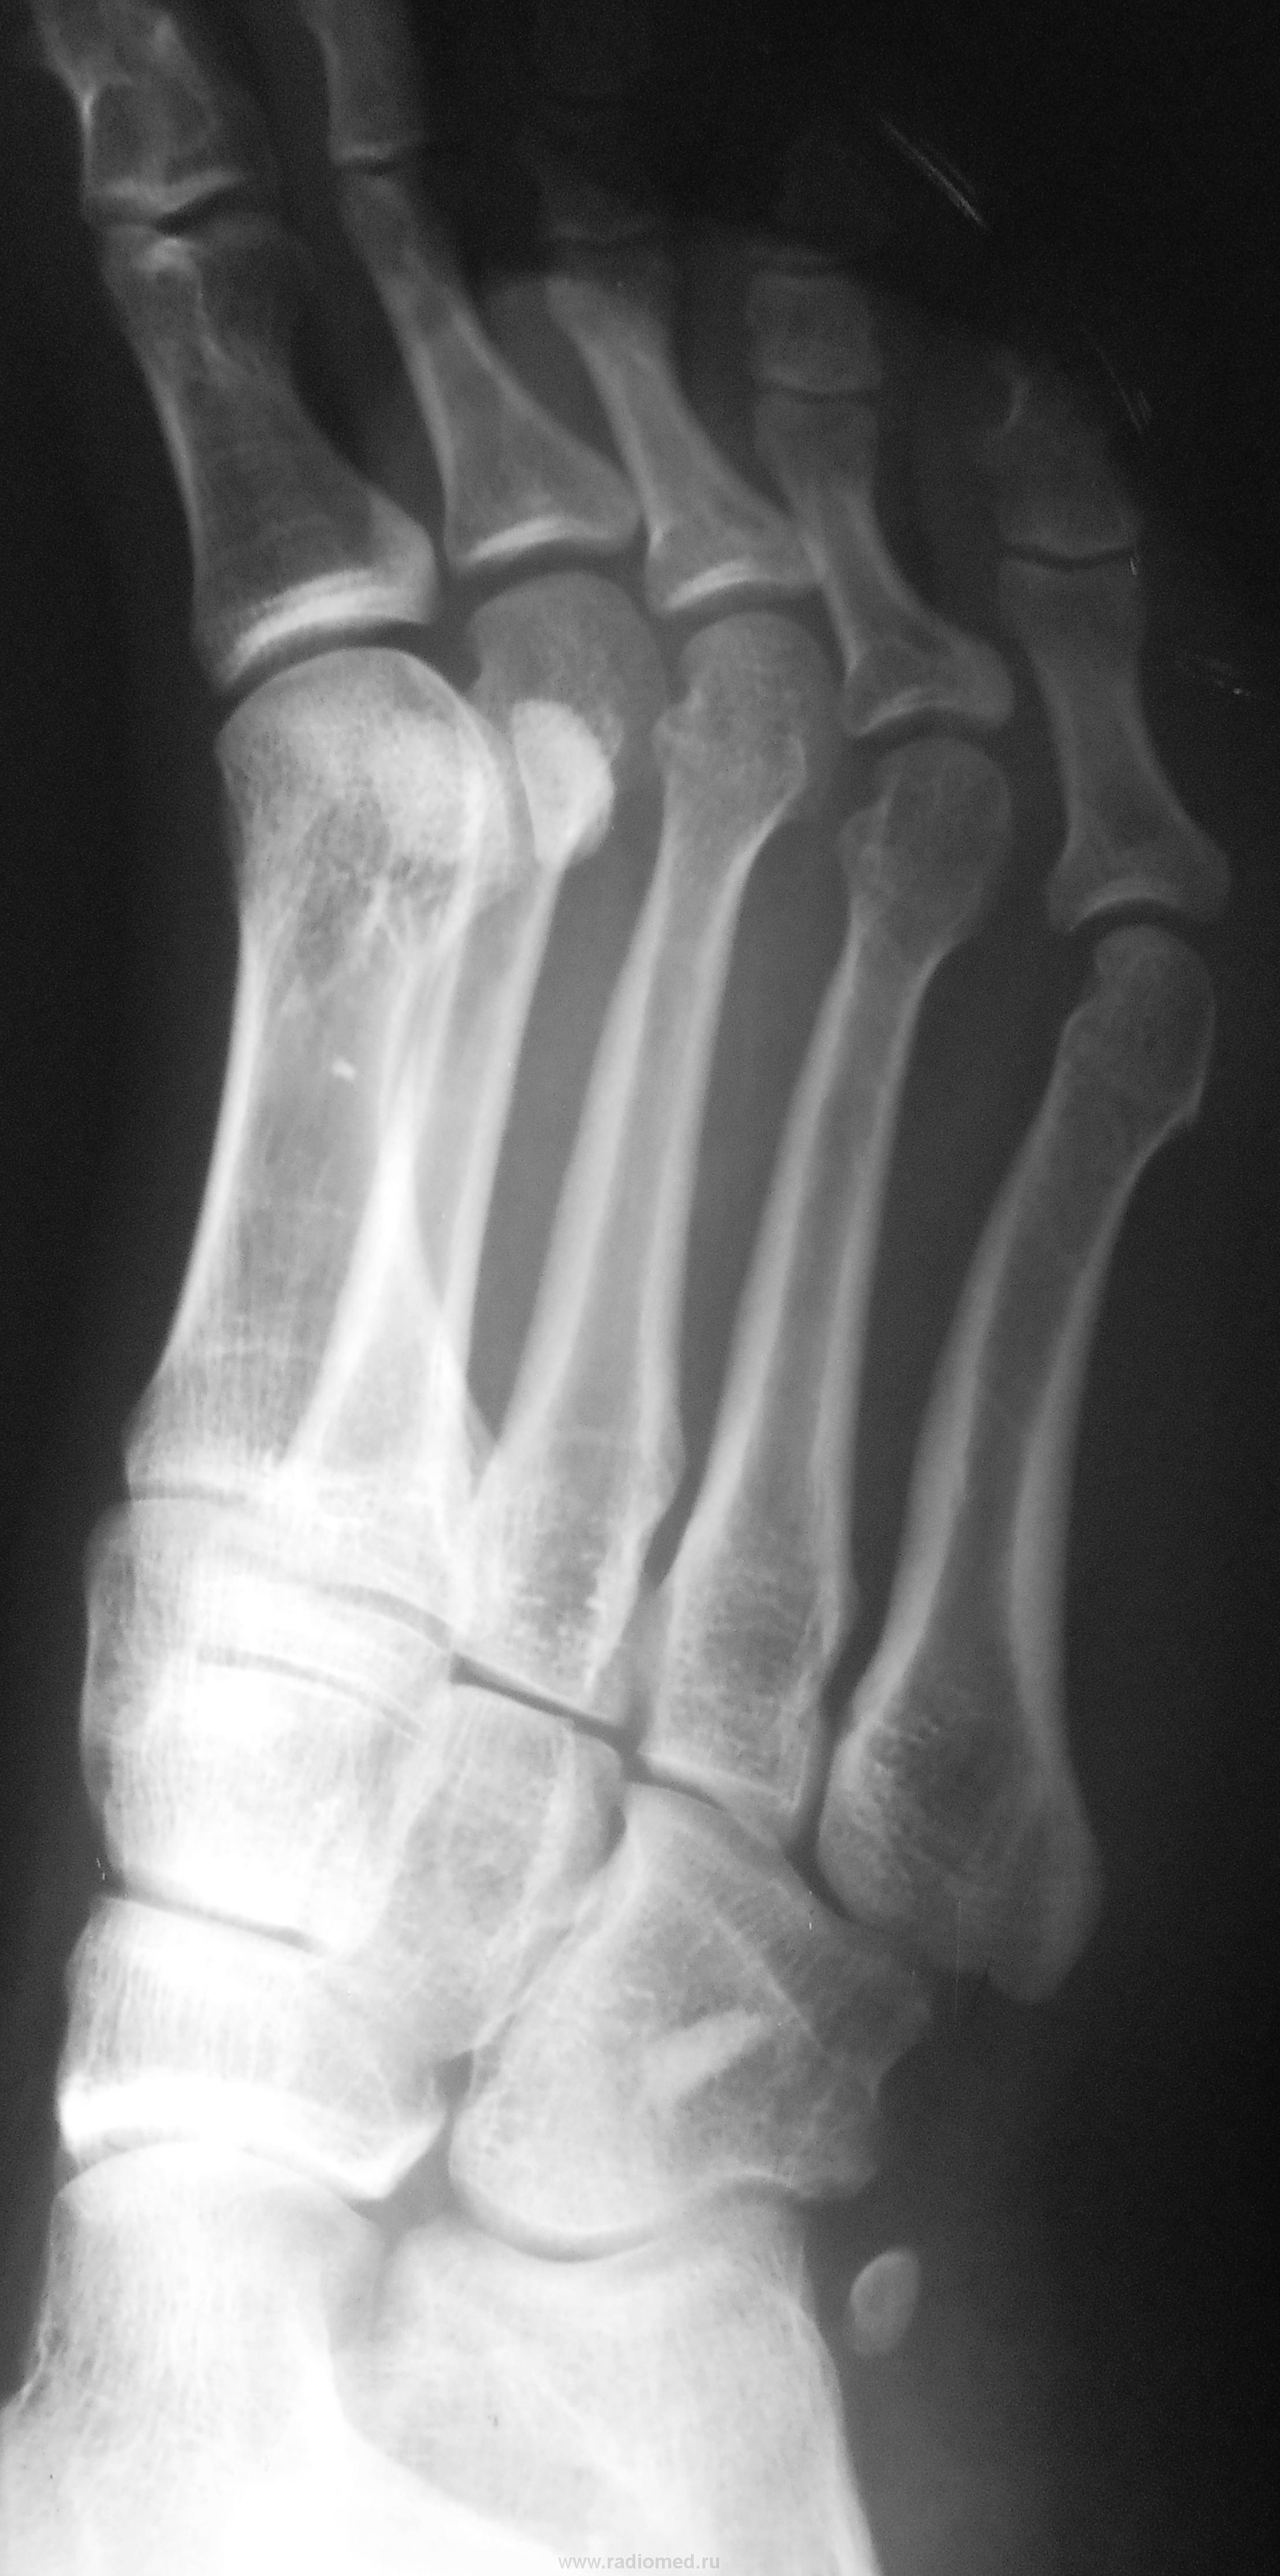

Пол пациента: Мужской пол Тип патологии: Травма Область исследования: Скелетно-мышечная система Методы исследования: Rg Травма. Пациент направлен на рентгенографию стопы. https://radiomed.ru/sites/default/files/styles/case_slider_image/public/user/12/2.dscn0128.jpg?itok=AhQao-28 https://radiomed.ru/sites/default/files/styles/case_slider_image/public/user/12/3.dscn0128a.jpg?itok=Nlxr5zQv https://radiomed.ru/sites/default/files/styles/case_slider_image/public/user/12/4.dscn0128ab.jpg?itok=wv8MneBo ID:23374 Втр, 25/09/2012 - 17:45 #1 Марина Сергеевна Не на сайте Был на сайте: 6 месяцев 3 недели назад Зарегистрирован: 26.04.2011 - 11:56 Публикации: 996 Какой четкий, склеротический контур... Это то, что в Королюке обозначено как внекомплектная os peroneum? Смущает склеротический очаг в кубовидной кости. "There is no teacher, who can teach us anything new. He just can help us to remember the things we always knew" (c) Enigma. Втр, 25/09/2012 - 18:51 #2 Наталия Васильевна Не на сайте Был на сайте: 5 лет 9 месяцев назад Зарегистрирован: 25.09.2011 - 09:02 Публикации: 754 Действительно, свехкомплектная кость, локальный склероз кубовидной.

Какой четкий, склеротический контур... Это то, что в Королюке обозначено как внекомплектная os peroneum?

Смущает склеротический очаг в кубовидной кости.

Действительно, свехкомплектная кость, локальный склероз кубовидной.